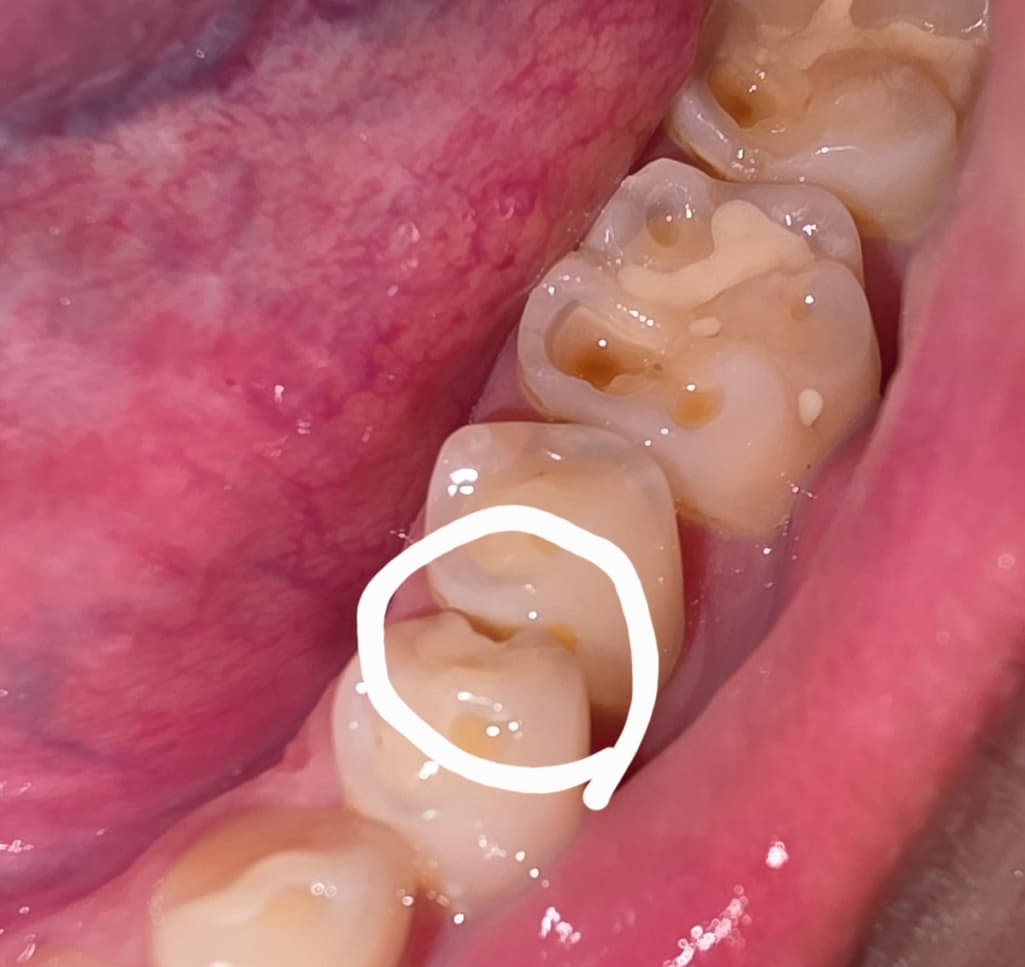

이가 깨진거같은데 치료가 복잡할까요??

이가 어느샌가 보니 홈이 생겨져 잇드라구요

동그라미 친부분 여긴 어떻게 치료하나요??....그냥 레진으로도 메꿀수잇나요??

치아 사이가 깨진거 같습니다. 충치가 심하지 않으면 인레이 치료를 하시면될것같습니다.

사진만으로는 알 수 없으며 해당 부위에 충치가 있을 가능성이 높아 간단하게 떼우긴 힘들 수 있습니다.

저 치아 뿐만 아니라 깨져나간 치아가 여러개 있네요 치료는 레진으로 떼우면 되는데 저렇게 다수 치아가 깨져나가는 원인(이갈이, 이악물기 등..) 을 찾아 개선해주면 더 좋을 것 같습니다

사진으로 봤을 경우 인접면에 충치로 인해서 파절이 된것으로 보입니다. 인접면에 충치가 있거나 충전제가 깨진것이라면 보철치료가 필요할수 있습니다.